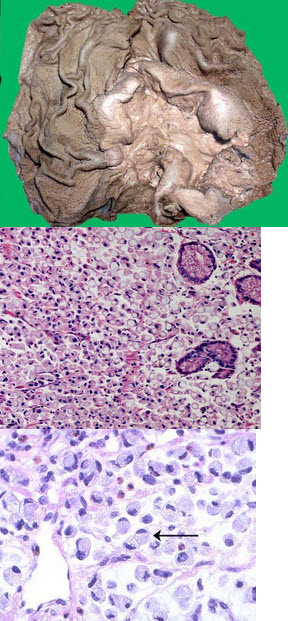

20、单项选择题

某患者,右上腹痛1小时入院,B超示胆囊肿大,内壁毛糙。手术切除胆囊送检。巨检胆囊7cm×5cm×3cm,腔内含泥沙样结石,内壁粗糙,壁厚0.3cm。镜下观如图,诊断为()

某患者CT示肝区有一3cm×3cm×2cm占位病灶,病检镜下观如图,以下诊断最可能的为()

A.肝硬化

B.原发性肝细胞癌

C.肝海绵状血管瘤

D.肝脓肿

E.以上均不是

肝穿刺送检标本,镜下如图所示,箭头所指肝细胞出现何种病变()

A.细胞水肿

B.脂肪变性

C.玻璃样变性

D.嗜酸性变

E.点状坏死